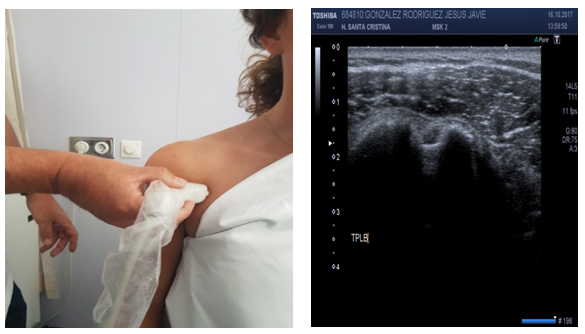

Dynamic Lateral view of the shoulder (subacromial impingement) (Figure 12)

Patient position: Patient is seated, shoulder in neutral position, arm at side and rotated internally and then lift the arm (abduction of the shoulder).

Probe position: Probe over lateral deltoid, longitudinal to upper arm.

Scan of structures: Supraspinatus tendon is seen as a beak-shaped structure protruding from under the acromion and attaching to the greater tuberosity.

Abnormal findings: A distance lower than 9mm from acromion to humerus may denote subacromial impingement.17–19

Figure 12 Subacromial impingement.